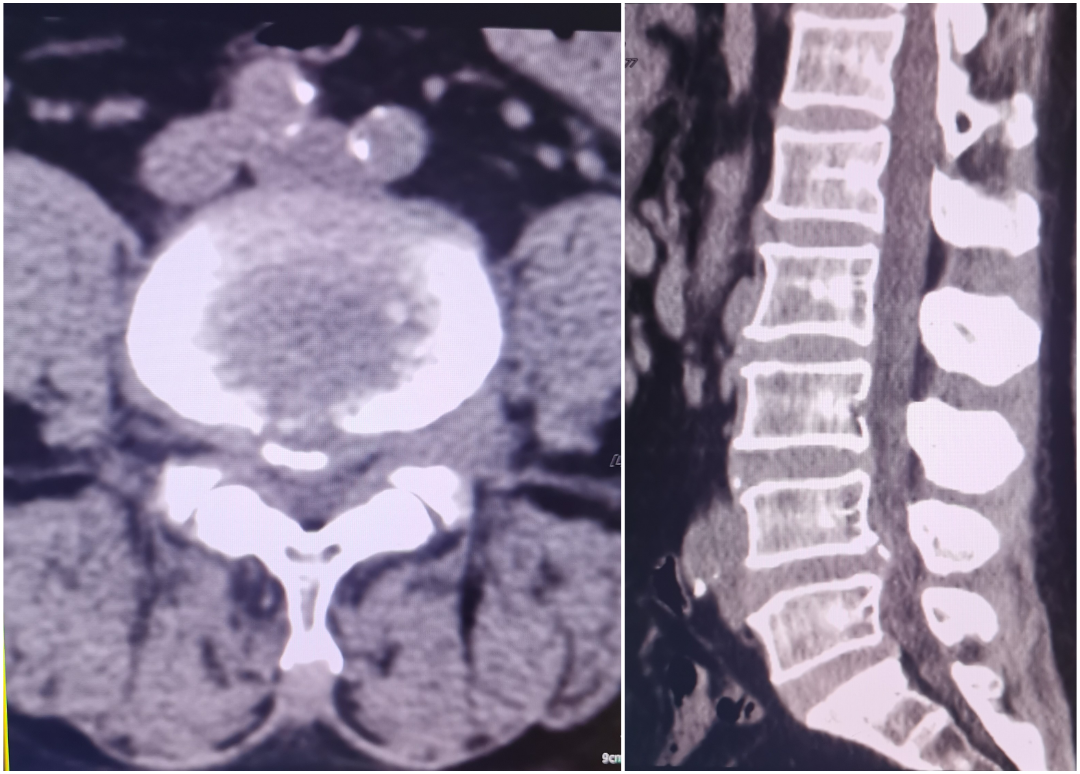

患者叶某,22岁男性,2月前劳动后出现腰部酸胀、麻痛,弯腰困难,站立行走、下蹲时明显,疼痛可向右大腿及小腿后侧及足底放射,平躺休息后缓解,症状反反复复,双下肢肌力感觉基本正常,结合辅助检查,诊断:腰5/骶1椎间盘突出,于局麻下行椎间孔镜下腰5/骶1椎间盘髓核摘除+神经根松解术,术后患者腰背部、右下肢无明显疼痛,术后第一天佩戴腰围下床自由活动。

术前CT、MR示:腰5/骶1巨大椎间盘突出

术后复查CT示:椎间盘已完全摘除